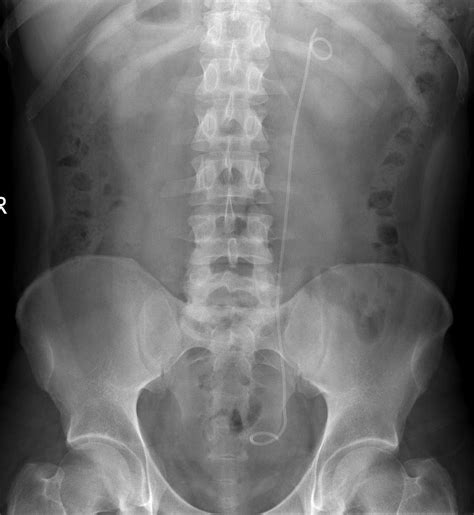

During the procedure, the urologist uses a cystoscope—a thin, lighted tube—inserted through the urethra into the bladder to locate the opening of the ureter. A guide wire is then passed through the ureter to the kidney. Once the position is confirmed via X-ray imaging, the stent is threaded over the wire and placed into the final position. The stent usually features small curls at both ends—one in the kidney and one in the bladder—to prevent it from migrating out of place.